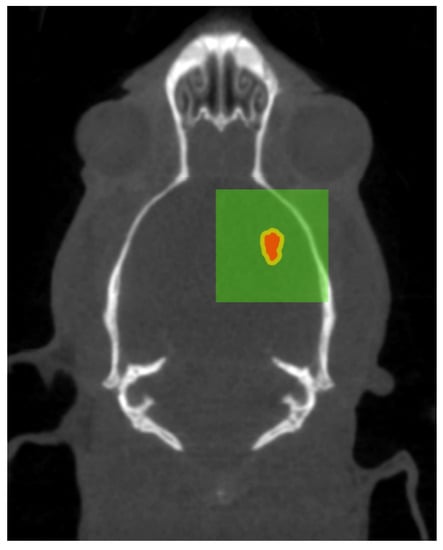

3.3. Image-Guidance in vivo Verification

The validation of the image guidance system was applied to an in vivo experiment described in Engels et al. 2020 [30]. As a means of validation of the targeting system, the position of the microbeam array relative to the centre of the tumour was measured using the brain histology of a rat in this study, 14 days after MRT. The complete use of animals is described in [30]. In brief, all animal procedures were performed within the guidelines of the National Health and Medical Research Council (2013) Australian code for the care and use of animals for scientific purposes and under the approval of the University of Wollongong and Australian Synchrotron animal ethics committees (AE17/05 and AS-2017-001). In total, 35, male, 8-week old rats were injected on day 0 with 10,000 9L gliosarcoma cells to the right caudate nucleus of the brain (3.5 mm to the right of the bregma crossing, and 6 m m depth). On day 11 these rats were imaged according to the method outlined in Section 2.8 using either the Inveon Multimodality System or SOMATOM go.Up, while under general anesthesia (2.5% isoflurane for maintenance and 5% for induction). To visualize the tumour within the CT scan, 1 mL of iodine contrast (Iomeron® 350, Bracco Ltd., Tokyo, Japan) was injected intravenously into the lateral tail vein using a Teflon 24G 3/4′′ catheter. On day 12, the identified centre of each tumour in 25 rats (the remaining 10 rats were controls) was aligned to the MRT treatment field and treated with an 8 mm × 8 mm field as described above. Figure 9 illustrates the intended treatment parameters as a result of the planning applied.

Figure 9. Coronal CT slice at 7 m m depth of tumour-bearing rat, one day before treatment. Overlaid gross tumour volume summed from all tumour depths (red), target volume with 0.34   m m treatment margins (yellow), and extremities of the planned 8 mm × 8 mm treatment field (green).